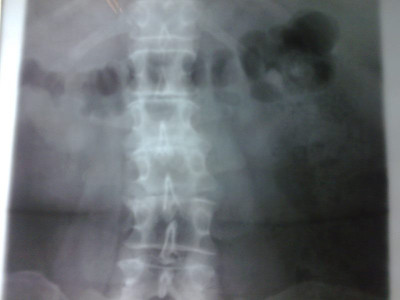

Radiografías con enfoque en fisiatría

Envíado por Dr. Hernán Darío Sánchez Ramos